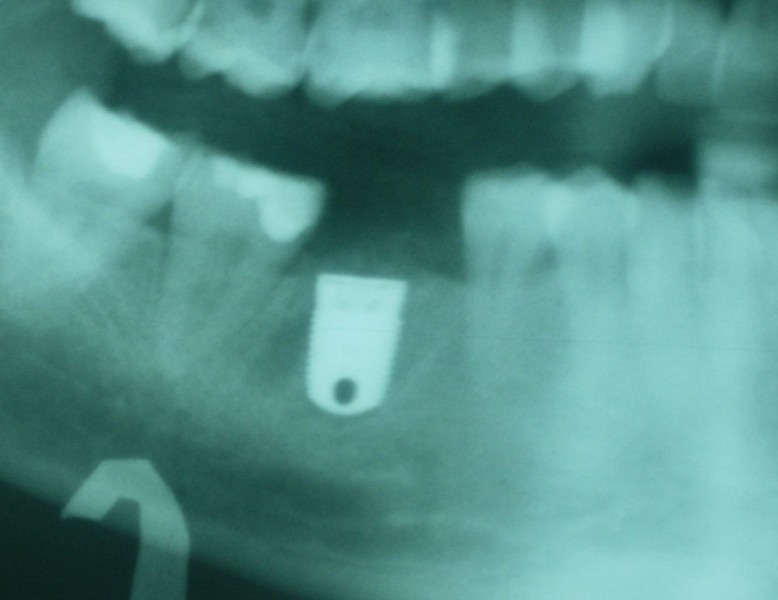

Immediate Molar Implant